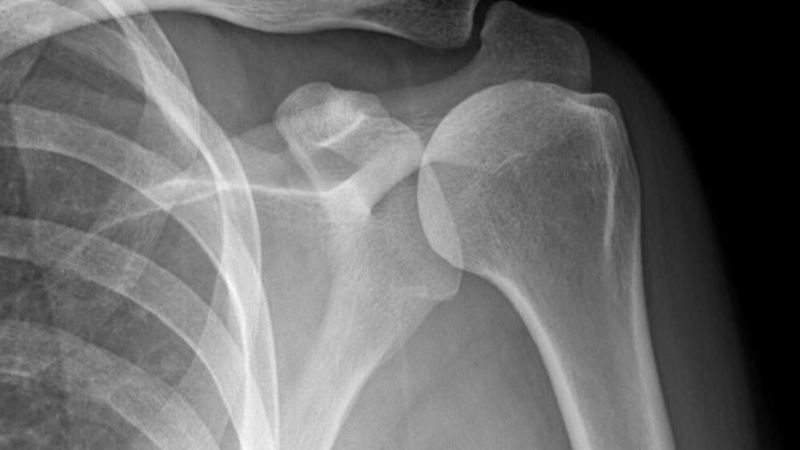

Để quan sát rõ hơn chấn thương vùng vai, người bệnh sẽ được chỉ định những phương phap sau:

- X-quang: Xác định có chấn thương vùng vai hay không.

X-quang dùng để xác định có chấn thương khớp vai không